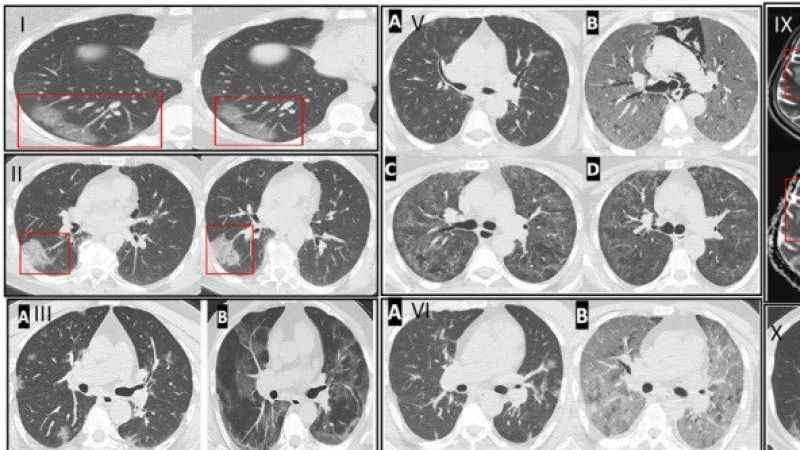

Prof. Dr. Şevket Özkaya, Altınbaş Üniversitesi Tıp Fakültesi Göğüs Hastalıkları Anabilim Dalı öğretim üyelerinin dahil olduğu 12 bine yakın COVID -19 hastasının incelendiği önemli bir klinik çalışma yapıldığını belirtti. Bu araştırmanın sonuçlarına göre COVID-19 virüsü ile enfekte kişilerde ve özellikle akciğer tutulumu olanlarda endotel hasarının görüldüğünün saptandığına işaret etti. Özkaya, özellikle pandemi ile damar hasarı ve tıkanıklıkların genç yaşlara inmesinin COVID salgını mı yoksa aşıların mı neden olduğu sorusunun ise hem tıp camiasında hem de toplumda tartışmaları devam ettiğini söyledi.

Prof. Dr. Şevket Özkaya buna göre, uzun süren hareketsizlik yani 2-3 saatten fazla oturarak hareketsiz yapılan yolculuklar, hastalıkların neden olduğu uzun süre yatakta olmak gibi kan akışının yavaşladığı durumlarda, ailesinde damar tıkanıklığı öyküsü olanlarda artık damar tıkanıklıklarının genç yaşlara indiğini vurguladı. Bunun birincil sebebinin COVID -19 virüsünün vücutta yerleştiğinde kanı oluşturan plazmayı, tahrip edici hale getirerek endotel denilen damarların en içteki katmanını tahrip ederek damar tıkanıklığının ilk basamağını ortaya çıkardığını anlattı. Bunun tetikleyici faktör olduğunun altını çizen Özkaya, “Aşılar bu hastalıkta bizi koruyan bir faktör idi. Genç yaşlarda damar tıkanıklıklarının görülmesi, aşılardan bağımsız ve öncelikle COVID -19 virüsünün etkileri ve bireysel faktörlere bağlıdır. Şunu unutmamak lazım; salgın bitti ama virus hala aramızda ve yeniden ağır ve kritik hastalar görmeye başladık” diyerek uyarılarda bulundu.